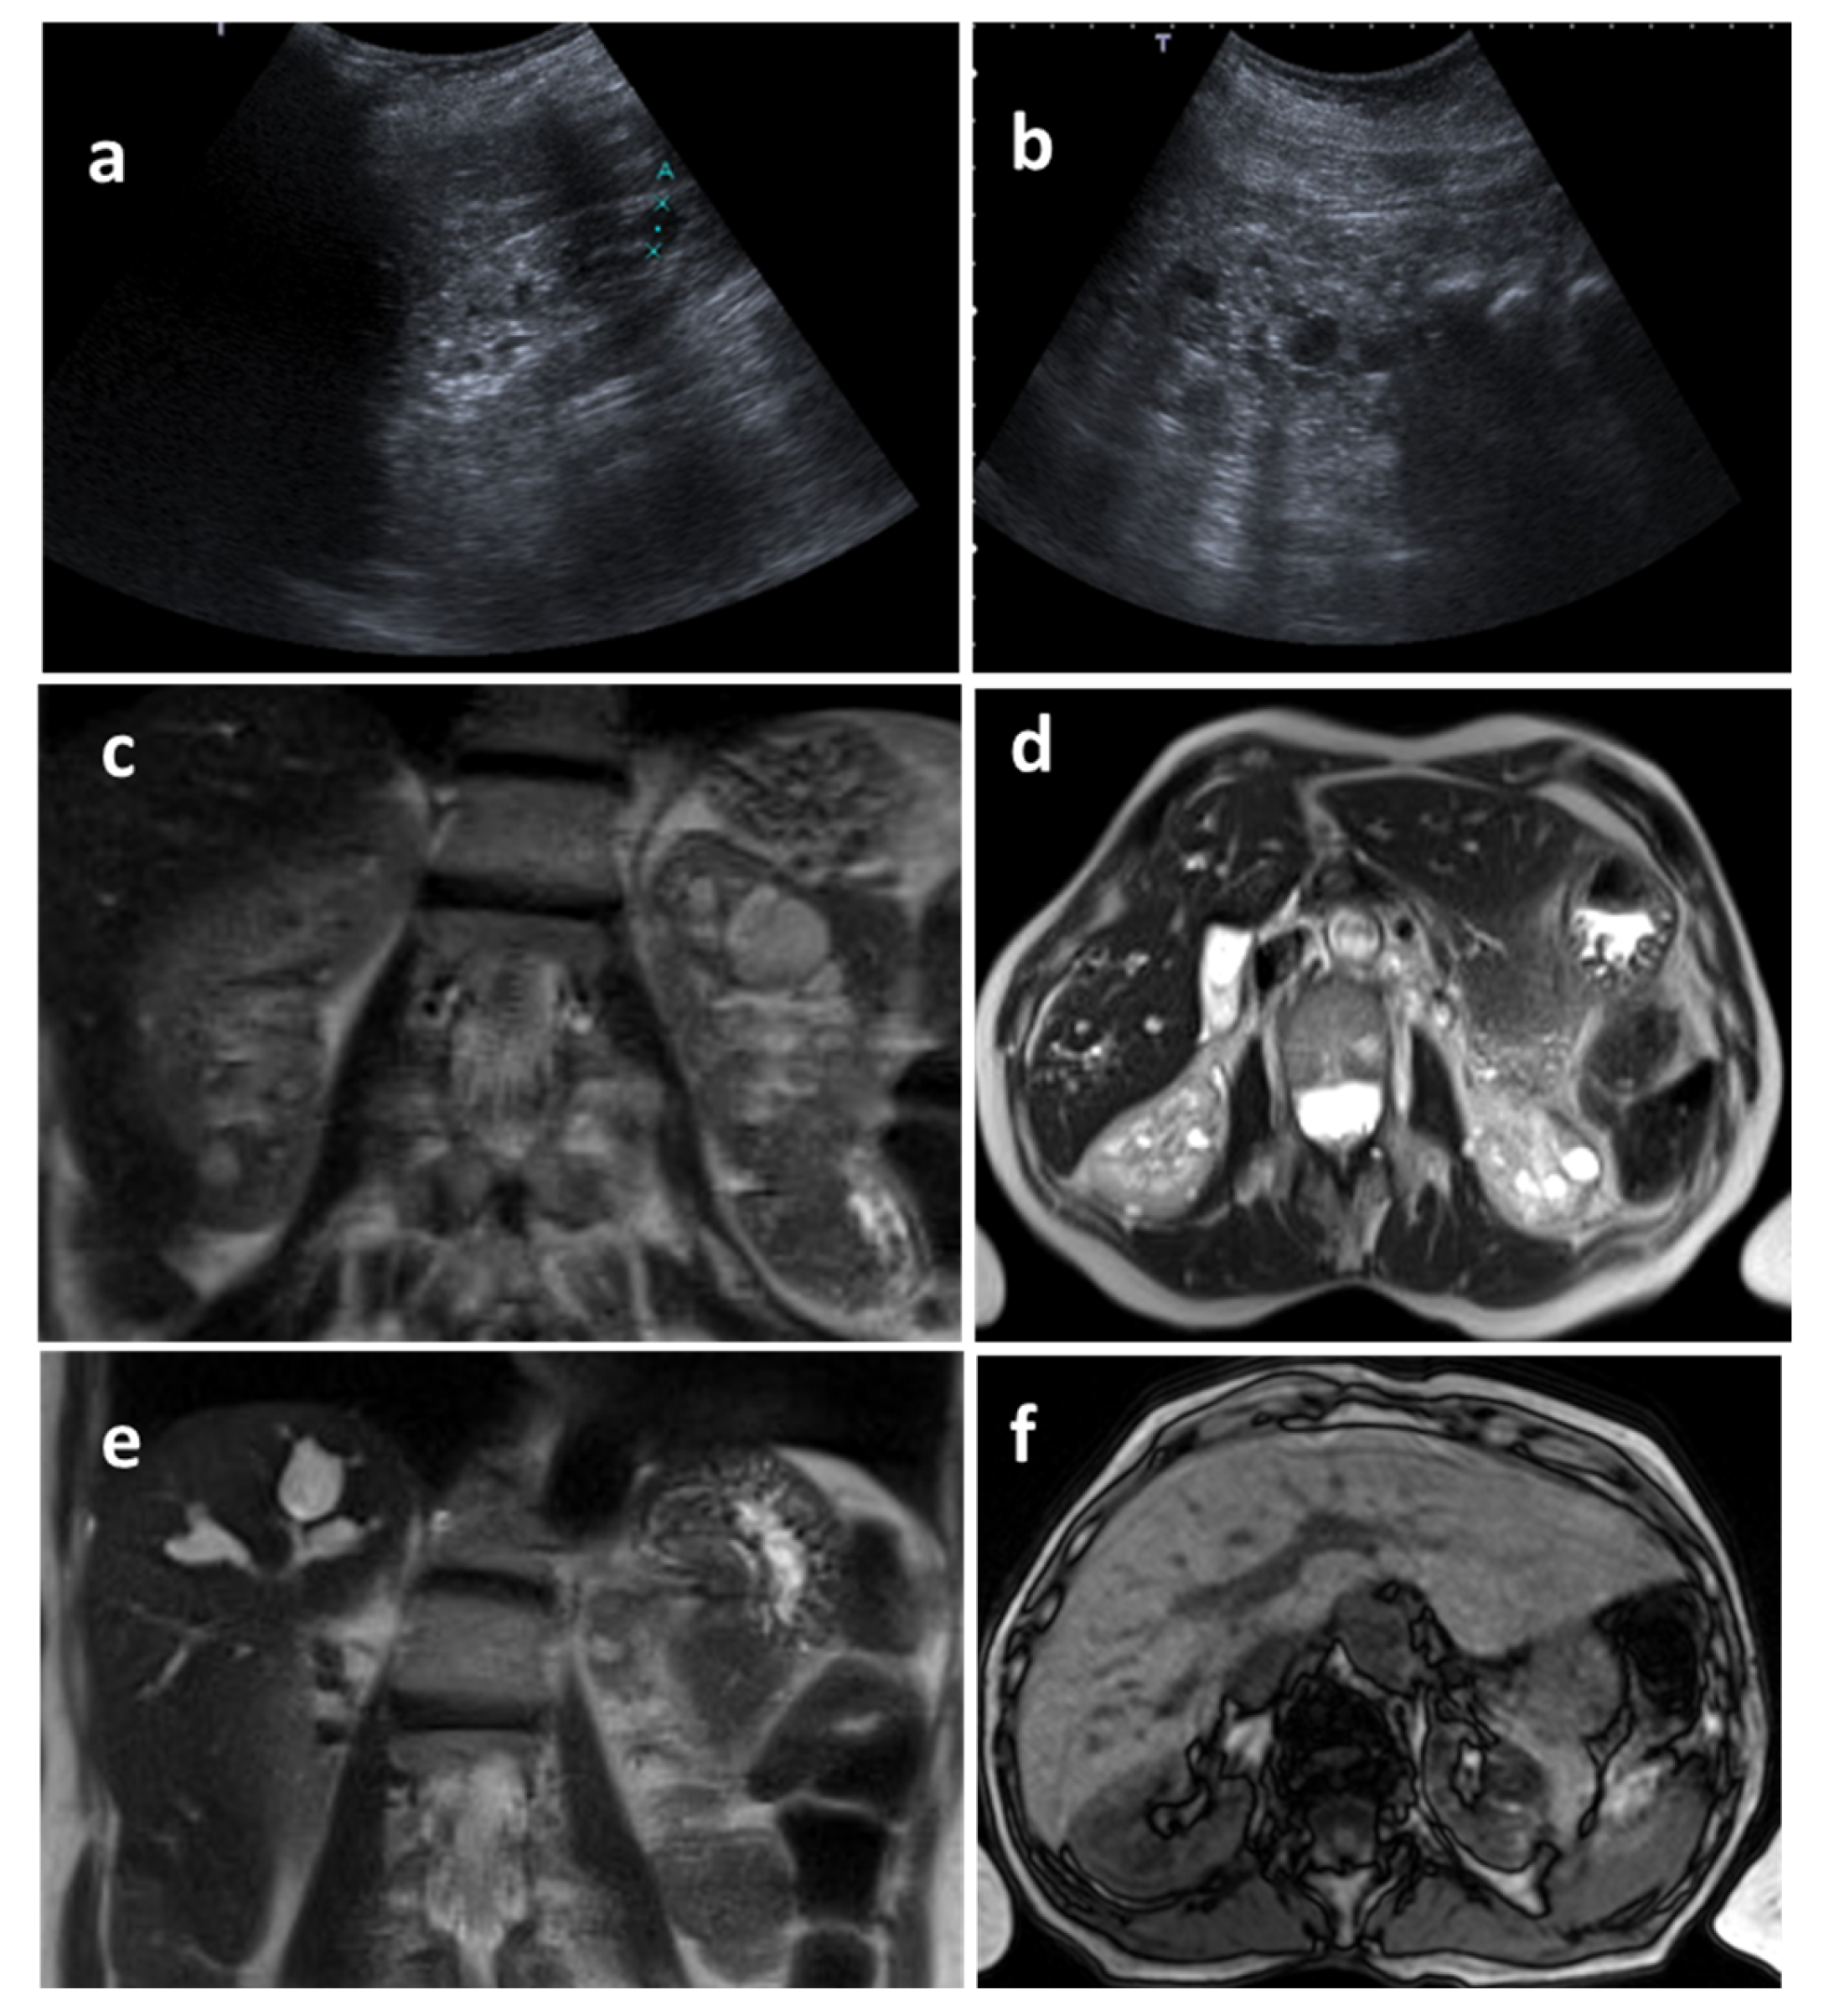

3.2. Imaging Characterization

Organ-Specific Findings

- Renal involvement

- Hepatic involvement